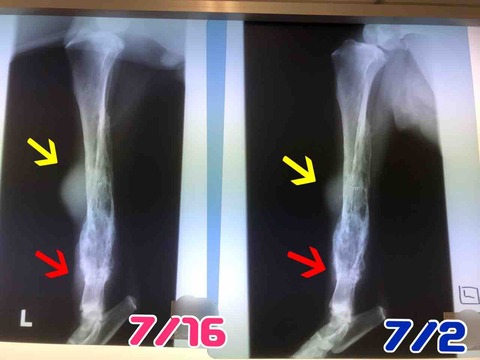

やっぱり、左後ろ脚と右前脚の検査結果は「腫瘍」でした。

細胞検査なので、何腫瘍かははっきりとはわからないけど、普通の骨肉腫とは違い特殊な腫瘍かと。

(腫瘍で骨が溶けてます)

右前脚も後ろ左脚も同じように骨が溶けてきているんだけど、後ろは腫瘍が大きくなるのがめちゃくちゃ早い。体調は良いです。

右前脚も後ろ左脚も同じように骨が溶けてきているんだけど、後ろは腫瘍が大きくなるのがめちゃくちゃ早い。